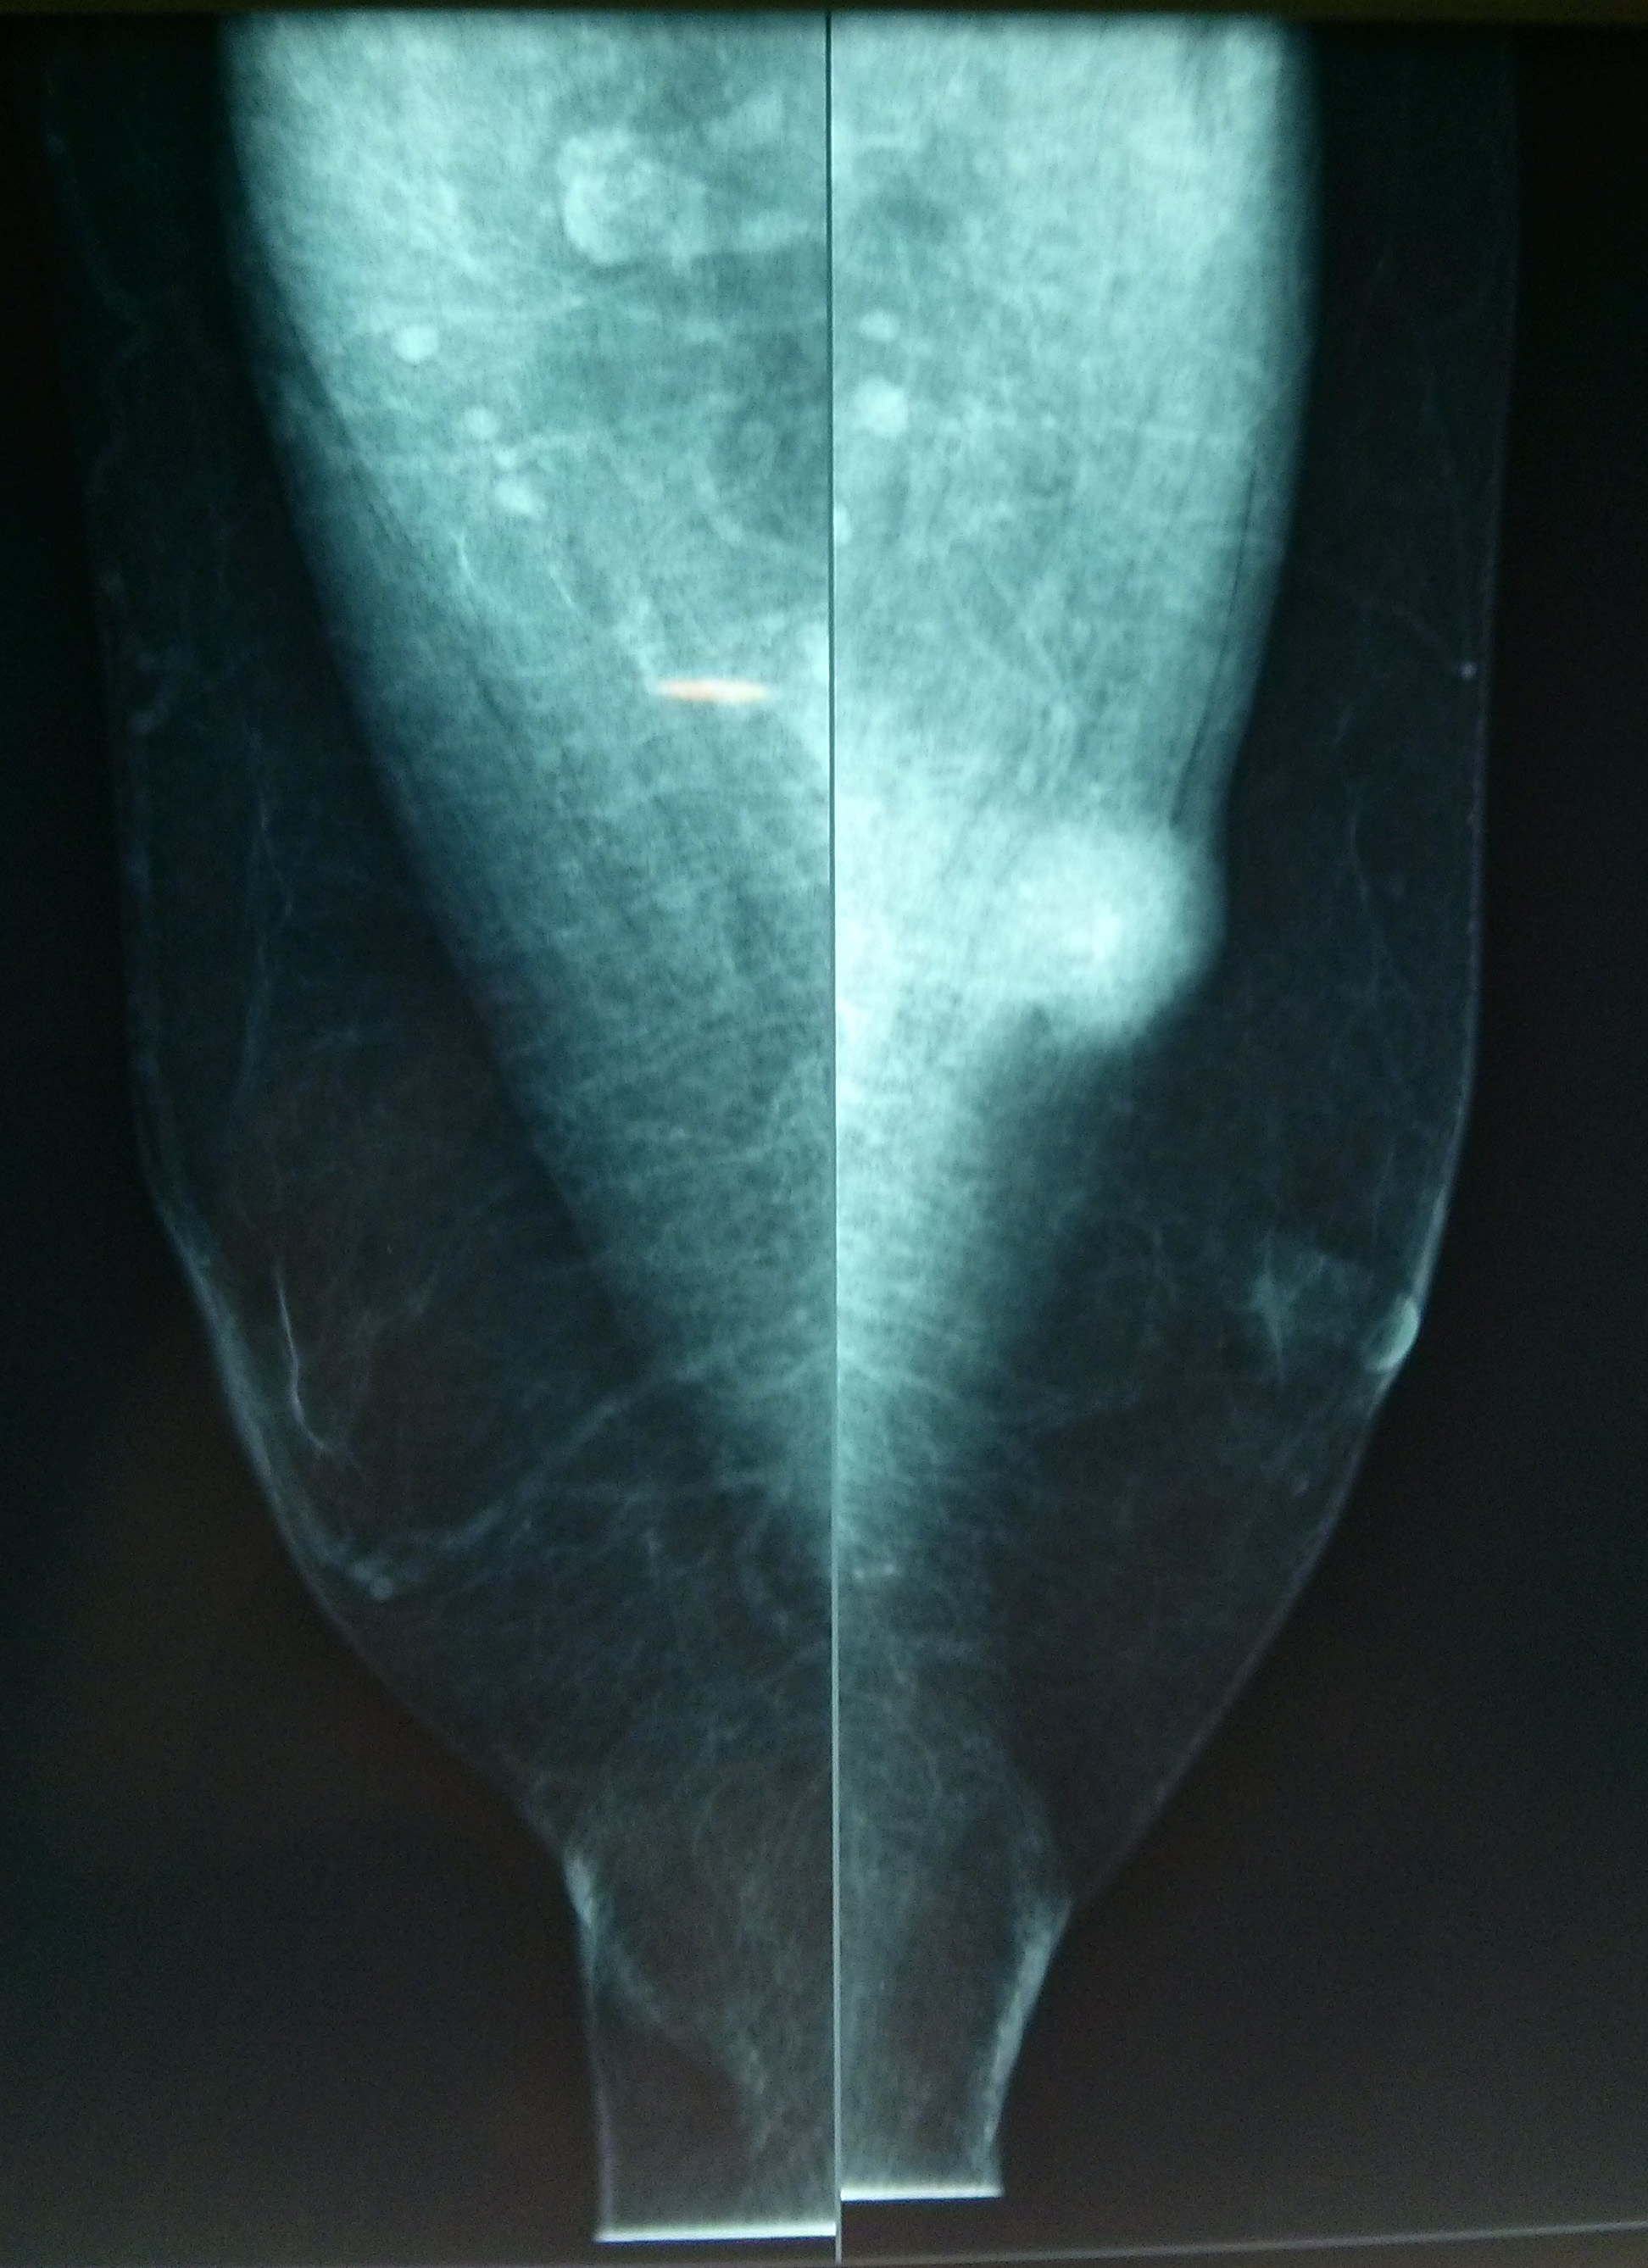

Dra. Mª Jesus Diaz Ruiz (radiòloga) i Dra. Carme Vergara Larrosa (Patòloga).

Althaia, xarxa assistencial universitària de Manresa

Dona de 50 anys, en cribatje de mama des dels 40; assimtomàtica. En una de les mamografies es troben calcificacions en QIE de mama esquerra de nova aparció.

En els controls succesius aparició de tumoració en QIE mama esquerra amb traducció radiològica de quist complicat de 13mm.

Es realitza PAAF: el diagnòstic es de abundant cel·lularitat inflamatoria, negatiu per cèl·lules malignes. Material citològic compatible amb quist.